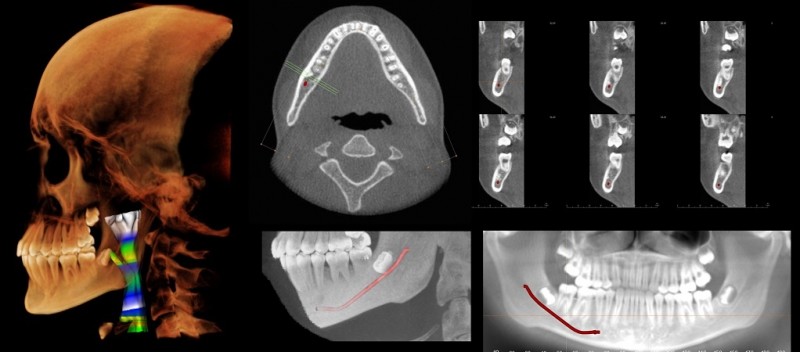

Imaging technologies such as MRIs and cone-beam CT scans, which produce a 3-D cross-sectional image, have expanded the ways dentists can explore beyond the teeth and gums. Panoramic X-rays, which capture the whole mouth in one two-dimensional image, are commonly used during checkups and to plan dentures, implants, braces, and extractions.

Ramesh, Panetta, and graduate engineering student Rahul Rajendran hope to teach the AI system to scan images—they are starting with panoramic X-rays—and flag areas that appear abnormal. Panetta has done similar work using AI to read mammograms or detect signs of cancer revealed by other kinds of medical imaging, as well as detecting diseases like COVID-19.